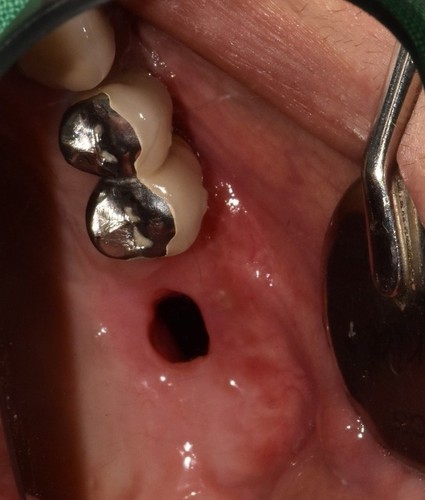

저희 치과에 오신 거는 발치한 날로부터 약 3주가 지난 상태로 오셨는데 발치한 치과에서는 한달이 안 되었기 때문에 더 기다려 볼 것을 권유 받으셨었습니다. 그런데 환자분이 제가 구강상악동누공에 대하여 작성한 포스팅을 보시고 저희 치과를 방문하시게 되었습니다. 보통 발치한지 3주가 되면 구강상악동천공의 단계를 지나서 구강상악동누공의 상태로 발전하게 됩니다. 내원 당시에 찍은 시티에서 10mm 이상의 천공이 확인 되었고 막아 놓았던 비흡수성 차례막을 제거하니 자연 치유될 정도의 천공이 아닌 걸로 확인하고 상악동누공폐쇄술을 시행하기로 하였습니다.

보통 5mm보다 작은 천공은 상악동염증이 없는 경우에는 자연치유 된다고 주장하는 논문도 있고 3mm 보다 작은 천공은 자연치유 된다고 말하는 논문도 있습니다. 하지만 제가 현재까지 약 30명 가량의 상악동누공폐쇄술을 했는데 환자 중에서 4mm 정도의 천공이 자연치유되지 않아서 폐쇄술을 한 경우도 2명 정도 있었습니다. 이걸로 보아서 5mm 보다는 3mm 보다 작은 천공이 자연치유 된다는 주장이 더 합당하다고 생각됩니다. 그래서 이 환자분은 10mm 이상의 매우 커다란 천공이 있었기 때문에 반드시 폐쇄술을 시행해 주어야 하지만 잇몸 상태가 너무 안 좋아서 잇몸이 어느 정도 치유될 때까지 기다린 후에 상악동누공폐쇄술을 계획하였고 성공적으로 잘 막혔습니다.